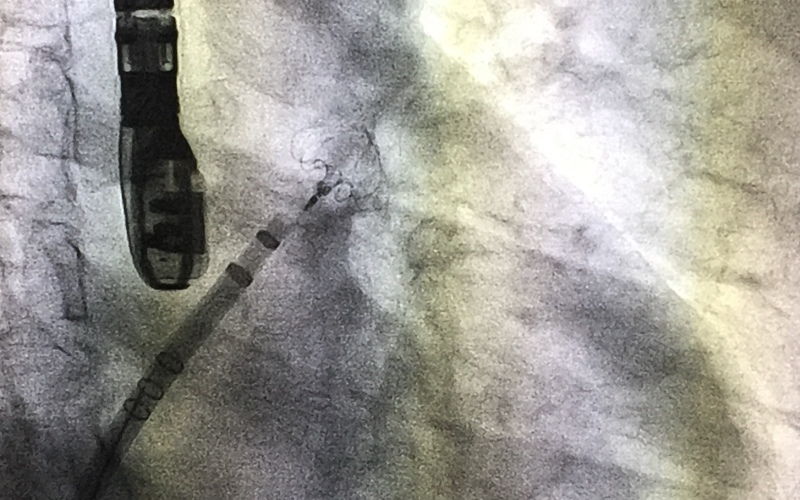

Crioablación: la cirugía que trata la fibrilación auricular con frío

A través del imágenes del procedimiento, el doctor Juan Benezet, responsable de la Unidad de Arritmias del Hospital La Luz, nos muestra cómo se realiza la crioablación, el tratamiento quirúrgico de la fibrilación auricular